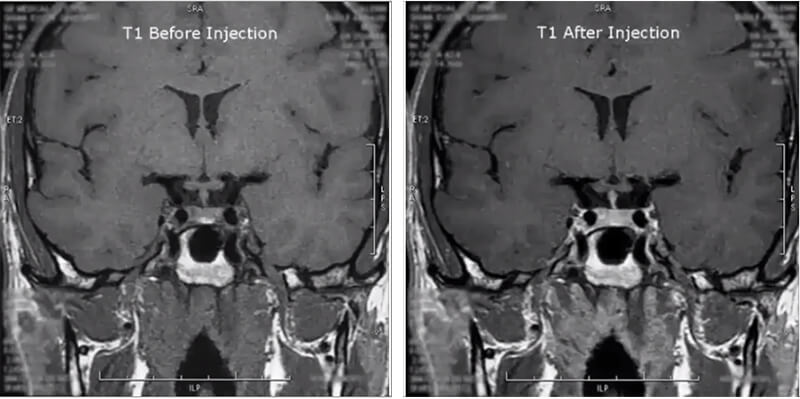

Next is a pituitary study. This image is a coronal T1 of the pituitary gland before and after injection. Notice how the contrast makes the pituitary gland highlight.